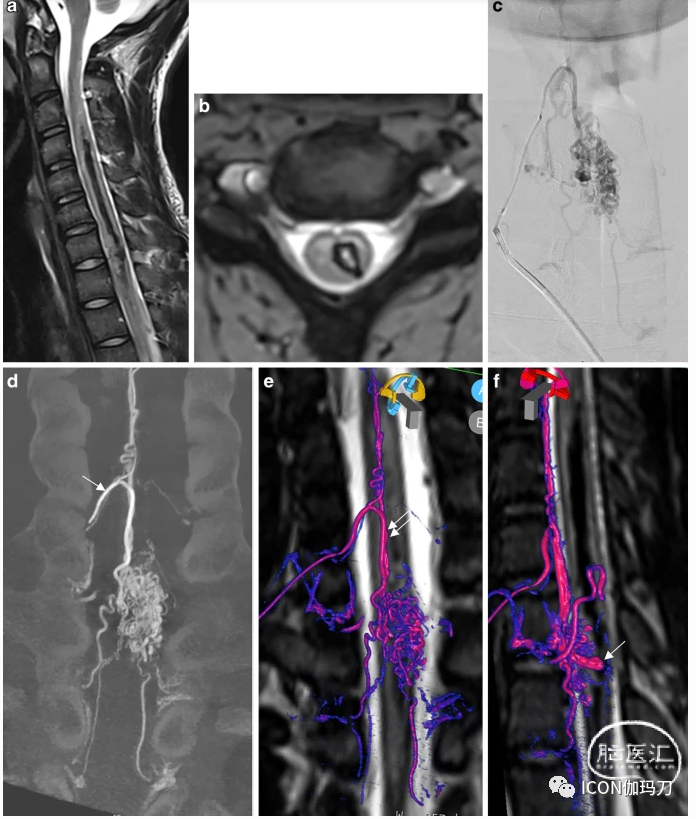

一位青少年因突然左侧偏瘫入院。脊柱MRI显示左侧血肿和位于脊髓内和颈胸交界处的多处血流空洞,提示脊柱动静脉畸形(图3)。DSA证实了这一诊断。颈动脉扩张的根髓动脉(Lazorthes动脉)是造成动静脉畸形的主要原因,它起源于右颈深动脉。另一条起源于上肋间动脉的根髓动脉供应动静脉畸形下部。DSA显示一个位于病灶内侧边缘的4 mm囊状动脉瘤。3DRA和各向同性T2w脊柱MRI融合显示动脉瘤位于脊髓中央部分,动脉瘤尖端位于血肿内(视频2)。在急性期,用线圈对动脉瘤进行靶向栓塞以防止再出血。(DSA前后位投影)。患者的临床恢复情况良好,除了右臂轻微无力外,无其余症状。

图3.破裂性脊髓动静脉畸形(AVM)合并大的内动脉瘤。T2W矢状面显示左侧大面积血肿。b血闪显示左侧脊髓内血肿扩大。c (DSA前后位投影)。d(冠状位重组3DRA)超选择性注射颈部肿大的主神经根髓动脉(Lazorthes动脉,箭头),显示一个大病灶和多条引流的神经根静脉。e, f三维旋转血管造影(3DRA)和T2W脊柱磁共振成像(MRI)融合显示供给脊髓根动脉的脊髓前动脉(双箭头),后者供给动静脉畸形(红色/粉色为动脉,紫色或蓝色为引流静脉)。膜内动脉瘤位于髓鞘中心,动脉瘤尖端指向血肿。补充视频演示了融合与嵌入式三维模型的AVM